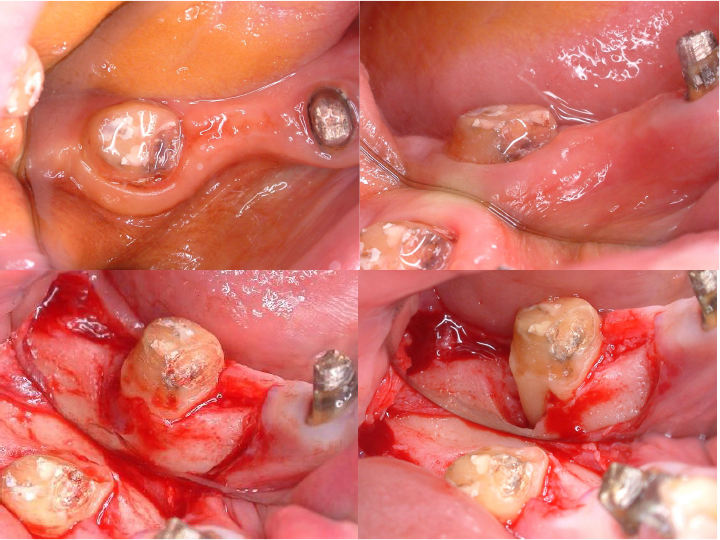

歯肉形成外科の術中所見です。最終的は被せもののイメージを行いながら歯茎と顎の骨の整形を行いました。

術前と術後の比較写真です。

歯茎の下の方まで虫歯でしたが歯茎の上までしっかりと健康な歯の部分を出すことができました。